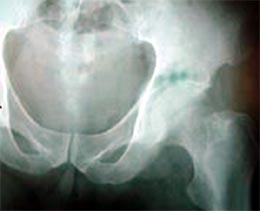

患者男性,52岁,左股骨颈骨折,曾经用空心钉和DHS固定,

两次手术均失败,股骨颈吸收,下肢短缩,疼痛,活动受限。

由于股骨近段两次手术均失败,导致股骨近段有骨质疏松骨缺损,

采用长柄的生物固定型股骨柄假体插入。

手术后X线片显示假体位置良好,双下肢恢复等长。患者功能恢复满意。